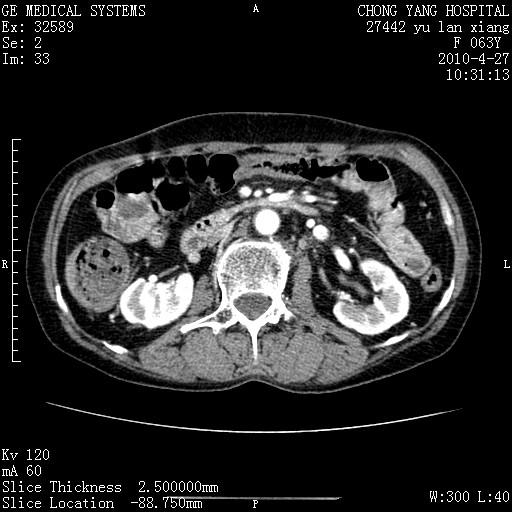

标题: CT26066:F63Y 上腹正中压痛半月,CA199:7400u/ml,MR示胰腺炎伴 [打印本页]

胰腺癌侵犯腹腔动脉干-分支、胃壁、左侧膈肌伴胰周及腹膜后淋巴结转移、胆囊切除术后。

胰腺癌侵犯腹腔动脉干-分支、胃壁、左侧膈肌伴胰周及腹膜后淋巴结转移、胆囊未显影。